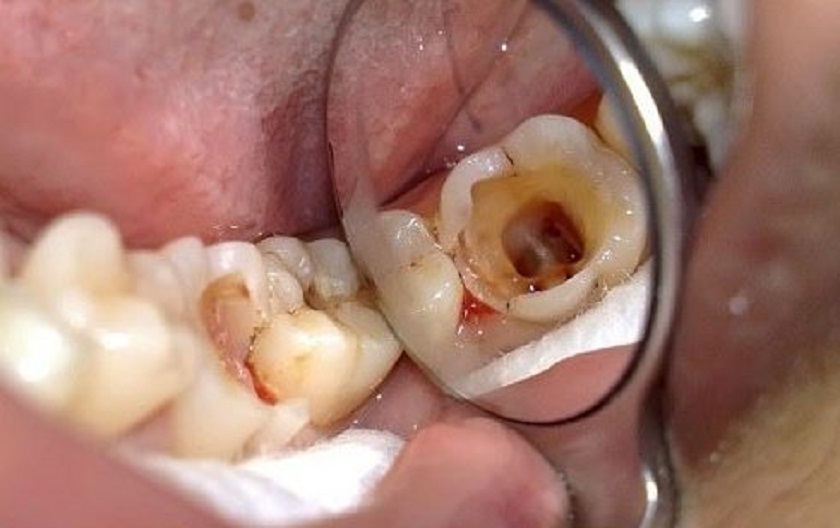

Răng sâu lỗ to là tình trạng răng bị sâu lâu ngày nhưng không có biện pháp xử lý kịp thời. Hậu quả là làm cho vi khuẩn lây lan rộng rãi và ăn mòn vào sâu hơn, hình thành các lỗ sâu có thể nhìn thấy được bằng mắt thường trên bề mặt răng.

Trường hợp sâu răng lỗ to thường xuất hiện nhiều nhất ở răng hàm. Bởi vì vị trí của những chiếc răng cối nằm khá sâu ở bên trong nên rất khó vệ sinh.

Cũng vì vị trí bị khuất nên khi các lỗ sâu nhỏ được hình thành thì các bạn cũng rất khó quan sát bằng mắt thường. Cho đến khi tình trạng sâu răng nghiêm trọng hơn và bắt đầu có triệu chứng như đau nhức, ê buốt thì mọi người mới chú ý đến.

Tình trạng răng sâu lỗ to